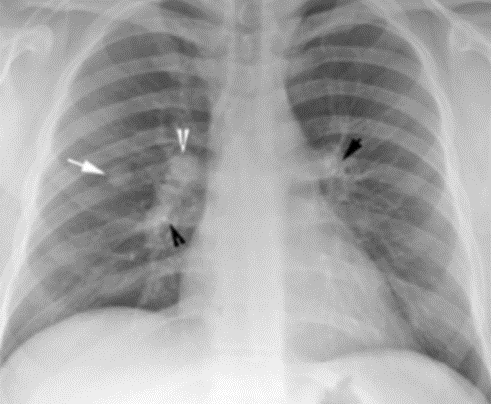

폐결절을 발견하는 방법으로는 여러 가지가 있습니다. 가장 기본적인 방법은 흉부 X선 검사입니다. 이 검사는 폐결절을 발견하는 데 유용하지만, 더 정밀한 검사가 필요할 때도 있습니다. 흉부 CT(컴퓨터 단층촬영)는 X선보다 더 정밀하게 결절의 크기와 위치를 확인할 수 있는 검사입니다. 또한 PET-CT(양전자 방출 단층촬영)는 결절의 대사 활동을 확인하여 악성 여부를 판단하는 데 도움을 줍니다.

폐결절을 진단하는 방법에는 여러 가지가 있습니다. 영상 검사는 가장 기본적인 진단 도구로, 흉부 X선, CT, PET-CT 등이 사용됩니다. 이러한 검사를 통해 결절의 크기, 위치, 형태 등을 파악할 수 있습니다. 또한, 조직 검사를 통해 결절의 일부를 채취하여 현미경으로 분석함으로써 양성인지 악성인지를 확인할 수 있습니다. 혈액 검사는 종양 표지자를 검사하여 추가 정보를 제공합니다.